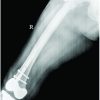

An 83-year-old woman had experienced right leg pain for approximately 1 year. She was diagnosed with lumbar spinal stenosis by a local doctor and had been consuming oral analgesics. She had a history of osteoporosis and had been receiving BPs (oral administration of minodronate for 1 year, intravenous alendronate for 1 year, and intravenous ibandronate for 3 years) and the active form of vitamin D analog (oral administration of eldecalcitol) prescribed by a local doctor for more than 5 years. She had no history of malignant tumors. She could walk independently with a T-cane; however, when she exerted weight on the left leg and lost balance, she felt severe pain in that leg and could not walk. She was subsequently admitted to our hospital. Her height, weight, and body mass index were 158.0 cm, 57.0 kg, and 22.8 kg/m2, respectively. Medical history included hypertension and cerebral hemorrhage that had resolved without sequelae. Radiographs of her left leg showed a short oblique fracture of the femoral diaphysis with a periosteal reaction, cortical thickening, and beak-like changes at the fracture site (Fig. 1).

The patient was diagnosed with an atypical complete left-sided femoral fracture. Subsequent CT revealed bilateral AFF, with an incomplete fracture of the right femur with cortical thickening and beak-like changes (Fig. 2). Blood tests showed no anemia (hemoglobin, 14.0/mL) and no abnormalities in calcium levels (9.7 mg/dL). BP administration was discontinued, and eldecalcitol was continued. Because the leg pain was considered related to lumbar spinal stenosis, surgery was planned only for the left-side complete fracture.